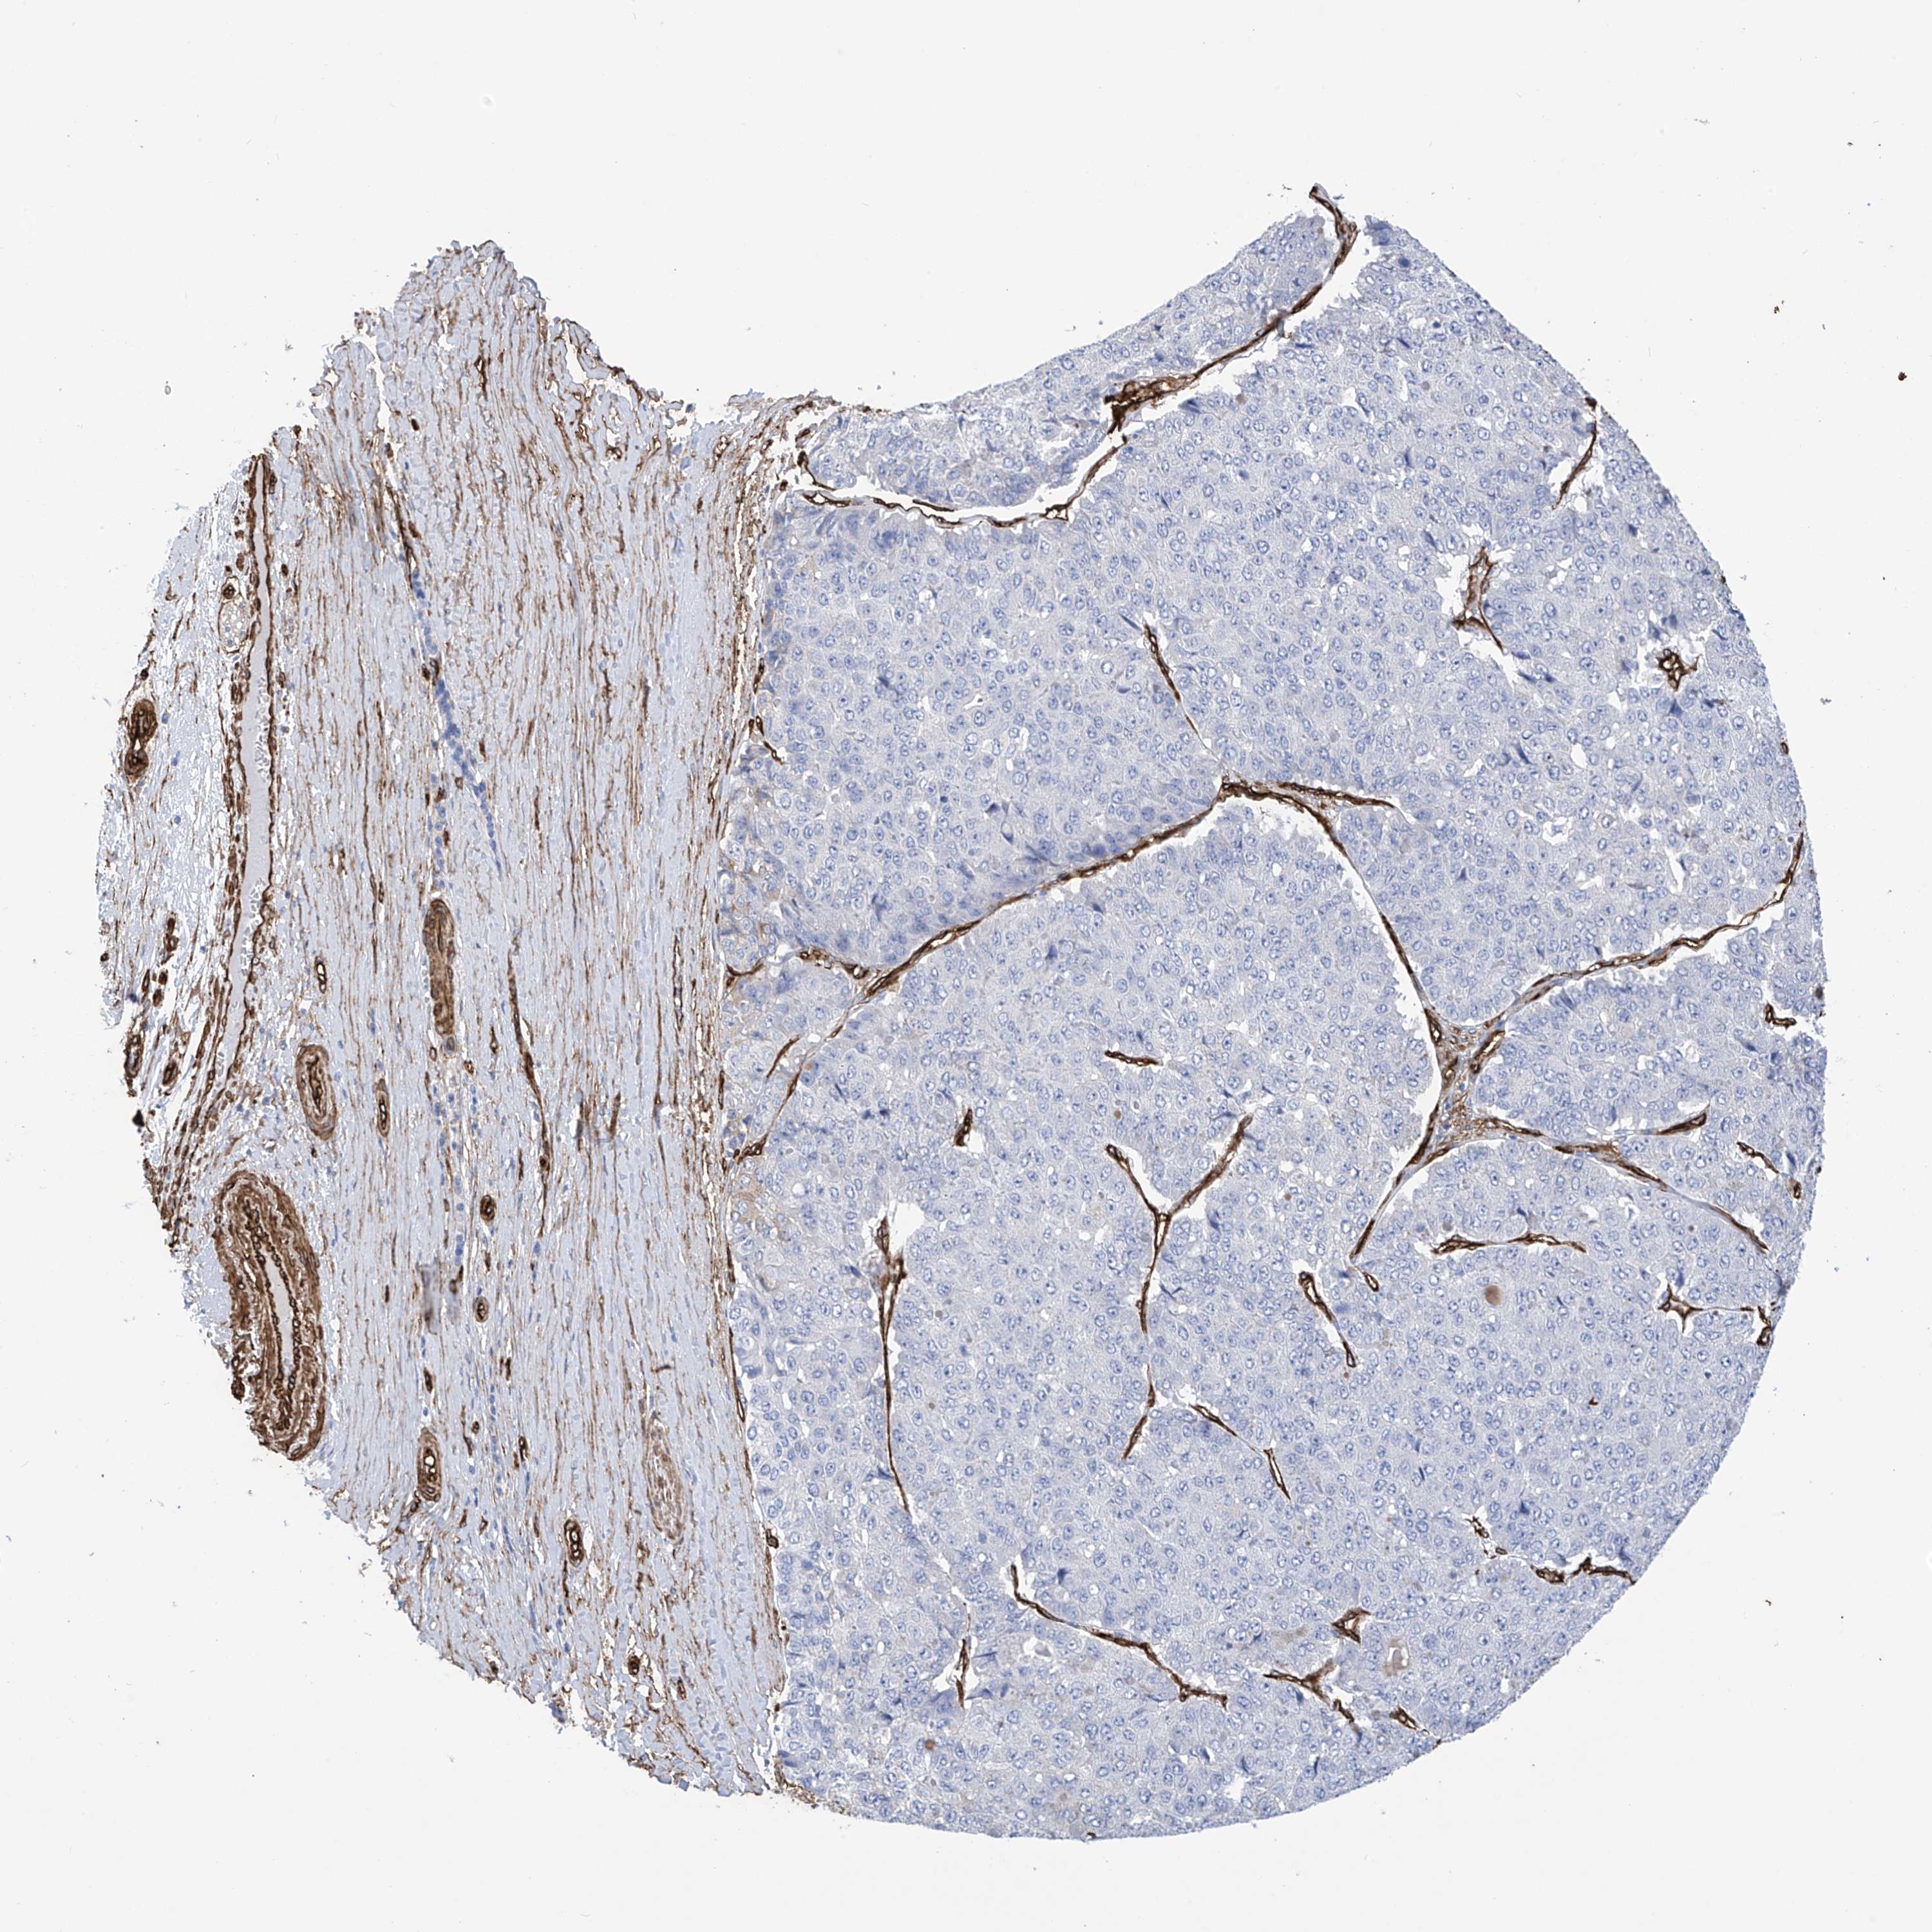

PANCREATIC CANCER - Protein expressioni

A mouse-over function shows sample information and annotation data. Click on an image to view it in a full screen mode. Samples can be filtered based on level of antibody staining by selecting one or several of the following categories: high, medium, low and not detected. The assay and annotation is described here.

Note that samples used for immunohistochemistry by the Human Protein Atlas do not correspond to samples in the TCGA dataset.

Antibody stainingi

Antibody staining in the annotated cell types in the current human tissue is reported as not detected, low, medium, or high, based on conventional immunohistochemistry profiling in selected tissues. This score is based on the combination of the staining intensity and fraction of stained cells.

Each image is clickable and will lead to virtual microscopy that enables deeper exploration of all samples and also displays staining intensity scores, fraction scores and subcellular localization as well as patient and tissue information for each sample.

Antibody HPA034825

Staining

High

Medium

Low

Not detected

Intensity

Strong

Moderate

Weak

Negative

Quantity

>75%

75%-25%

<25%

None

Location

Nuclear

Cytoplasmic/membranous

Cytoplasmic/membranous,nuclear

Adenocarcinoma, NOS